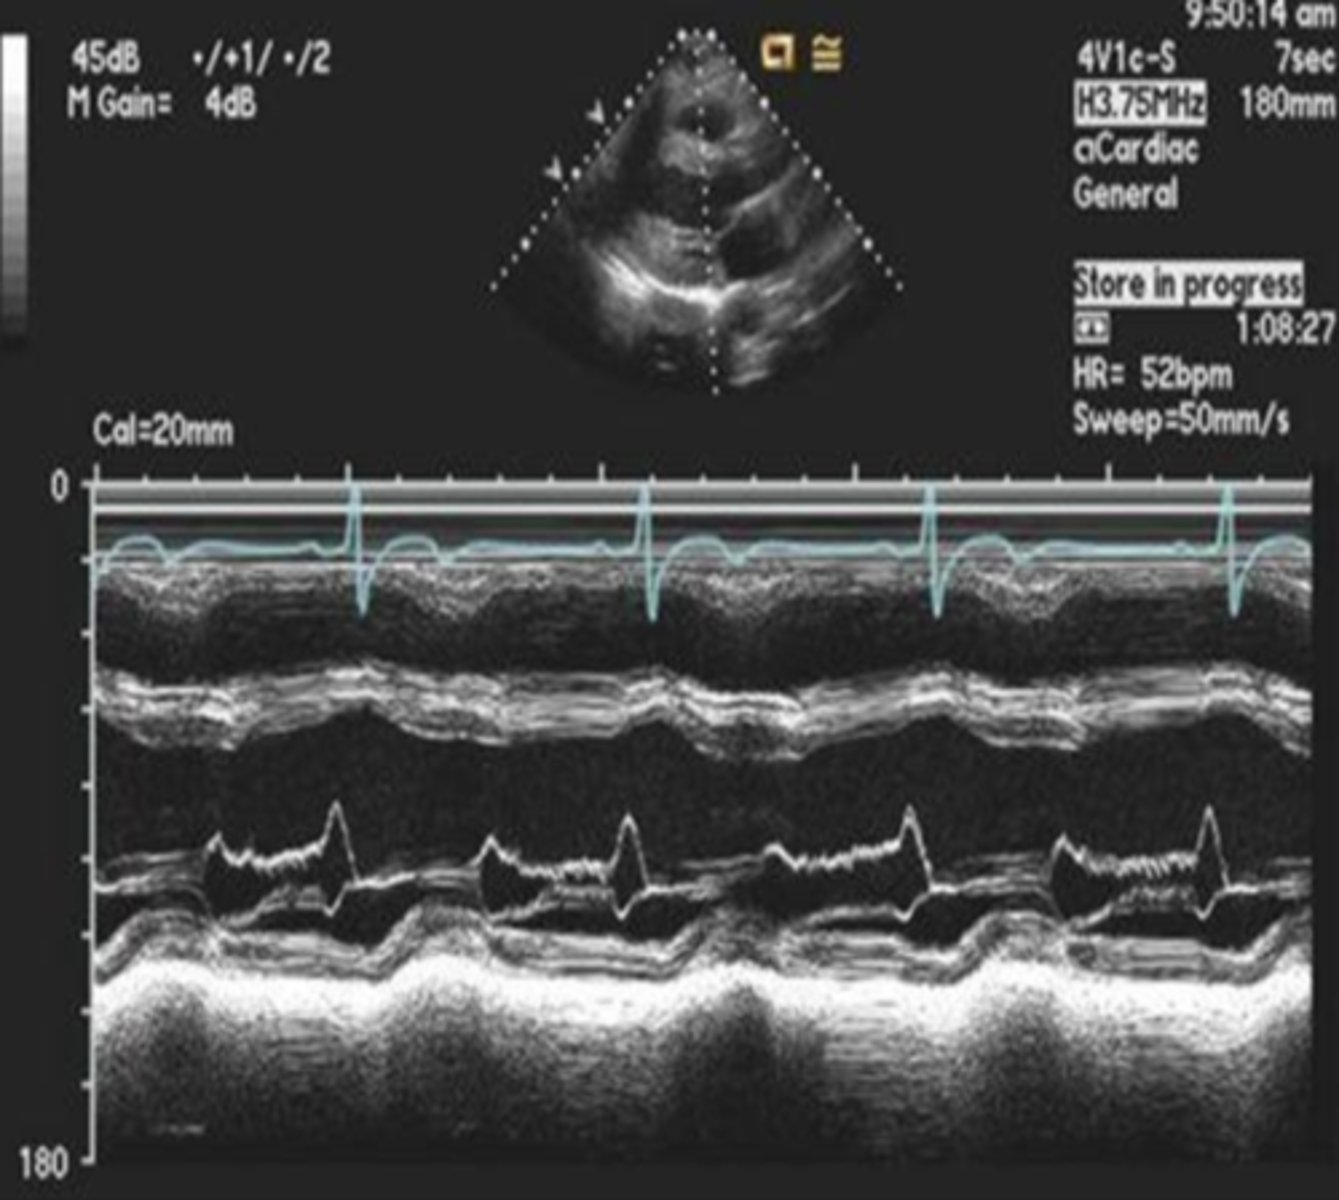

MV leaflets move anteriorly towards the LVOT in systole; seen in hypertrophic cardiomyopathies such as ASH, IHSS, HOCM, and subaortic outflow tract obstruction

systolic anterior motion (SAM)